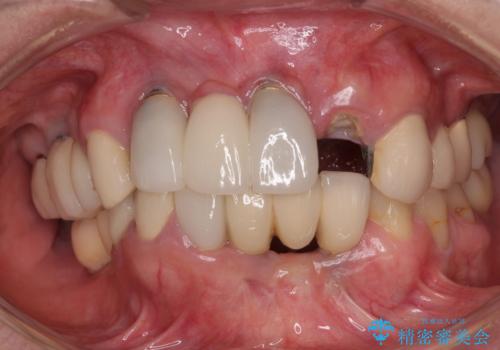

- 失活により変色した歯と不揃いな口元を気にして来院された患者様です。

口元をインビザラインにより歯列を整え、その後に失活している奥歯をオールセラミッククラウンにて補綴治療することとしました。

長時間のマウスピース装着と、患者様自身でのゴムかけに協力いただき、自然な口元に仕上げることができました。

気になっていた変色した歯もオールセラミッククラウンで本物の歯のようになり、患者様には大変満足していただきました。